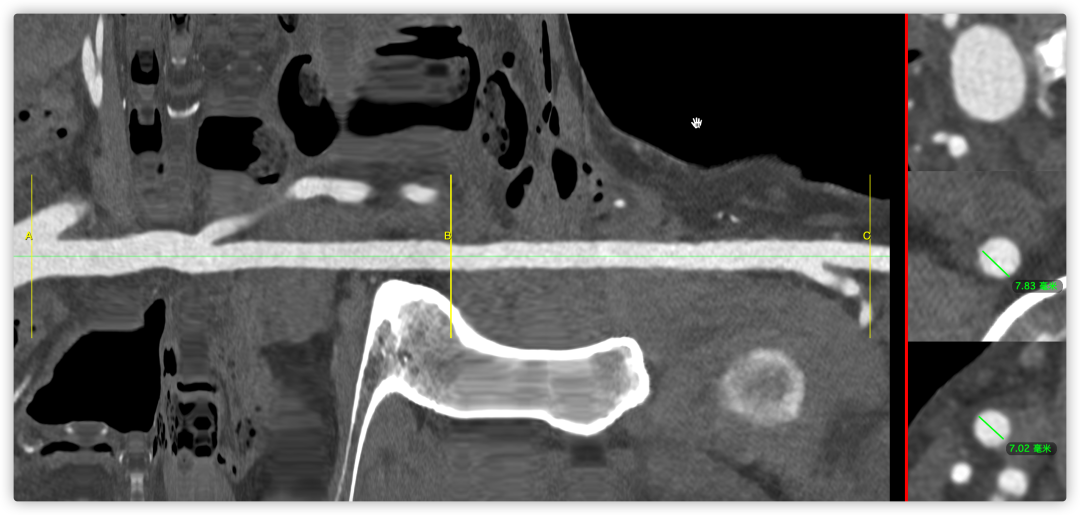

根部角度/瓣环/左室流出道

瓣上结构2,4,6,8,10,12mm

SOV/STJ/AAO

左冠风险评估